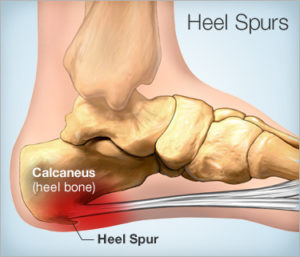

Calcaneal Spur And Its Homoeopathic Miasmatic Approach

Author:Dr Vishnu T MAssistant Professor, Dept. of Anatomy,Yenepoya Homoeopathic Medical College and HospitalNaringana, MangaloreKarnataka Calcaneal spur is a spike of bone at the anterior edge...